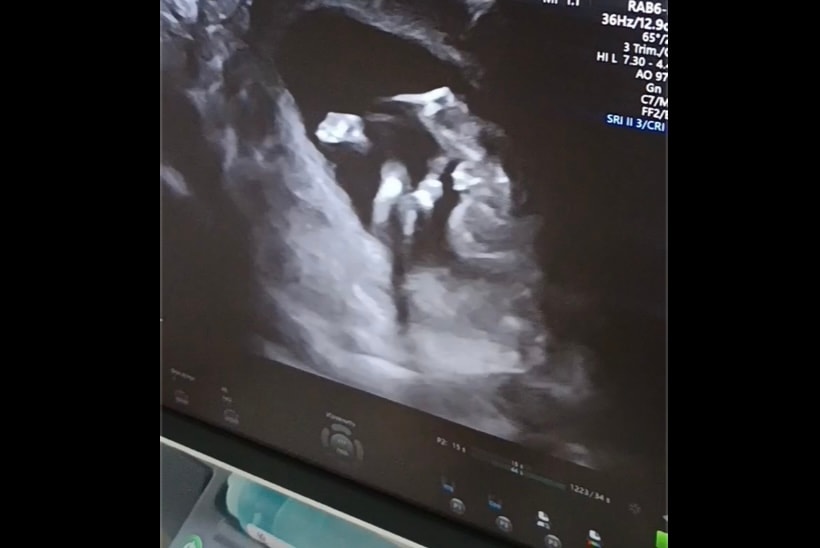

Изображение Изображение

Василиса , я вижу мошонку. Мои девочки выглядели по-другому на УЗИ. Там было чёткое кофейное зёрнышко. По центру была темная полосочка, а не светлая